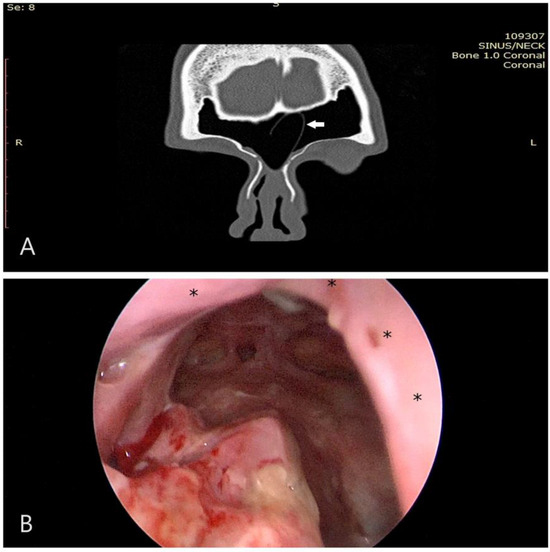

Figure 3. (A) CT scan of the same case, taken 3 weeks postoperatively. Observe the presence of the silastic sheet (indicated by the white arrow); (B) subsequent follow-up image, captured 6 weeks postoperatively. The neo-ostium is prominently open, and the flap is thoroughly integrated (asterisks).